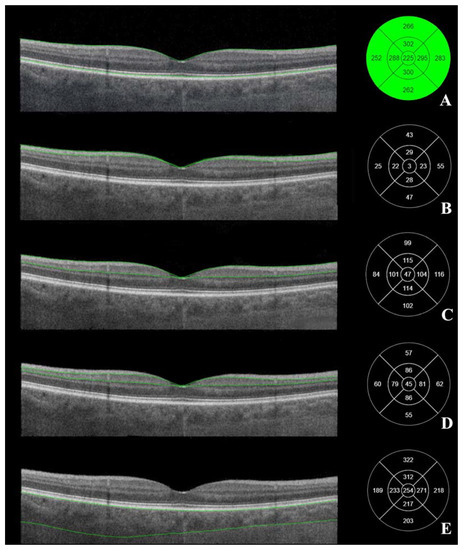

3.2. Posterior Segment OCT Results before the Cataract Surgery

3.3. Posterior Segment OCT Results Six Months after the Cataract Surgery

3.4. Comparison of Posterior Segment OCT Results before and Six Months after the Cataract Surgery